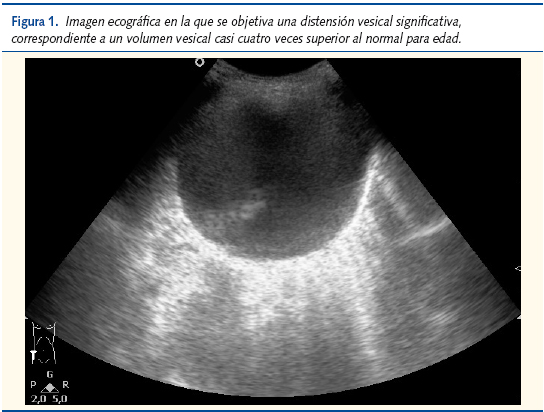

No obstante, al realizar la ecografía abdominal se constató que no había, en apariencia, imágenes de invaginación intestinal. Destacaba, por el contrario, una marcada distensión vesical (hecho que podía interferir con la correcta visualización de las asas). Para una niña de dos años de edad, el volumen medio de la vejiga urinaria es de aproximadamente 120 ml3; esto es, 3,75 veces menos del volumen encontrado2.